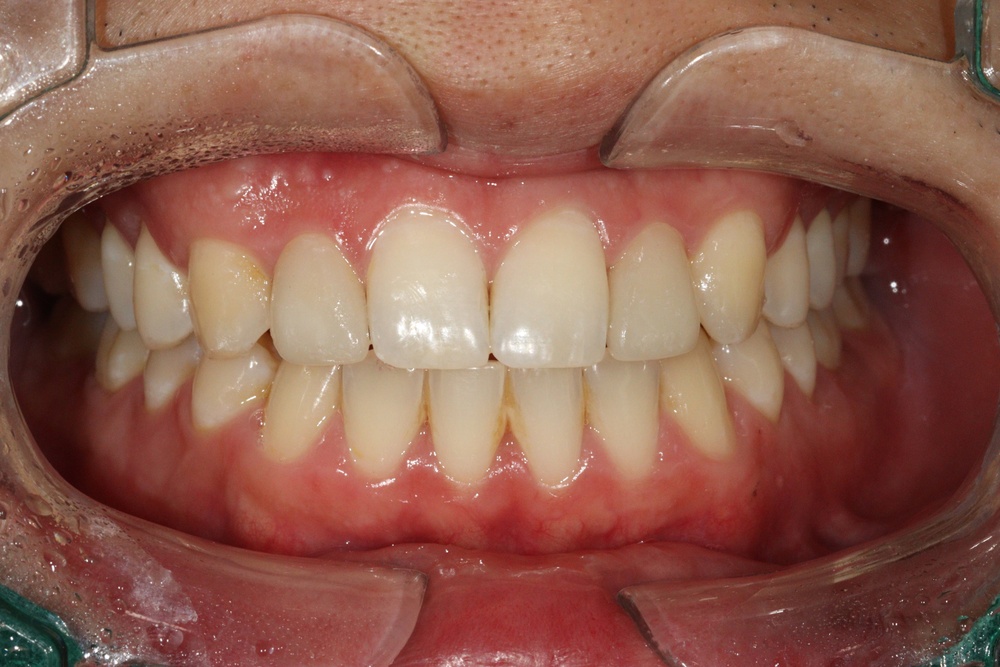

치아 배열이 거의 완성된 상태로 치료 전 말씀드렸던 치아사이의 틈(블랙트라이앵글)이 있습니다.

환자분과 상의 후 위쪽은 벌어진 공간을 레진으로 메꾸기로 하였습니다.

치아가 가지런해졌고, 윗니 치아 사이의 틈도 메꿔졌으며, 치아에 있던 충치도 모두 치료하였습니다.